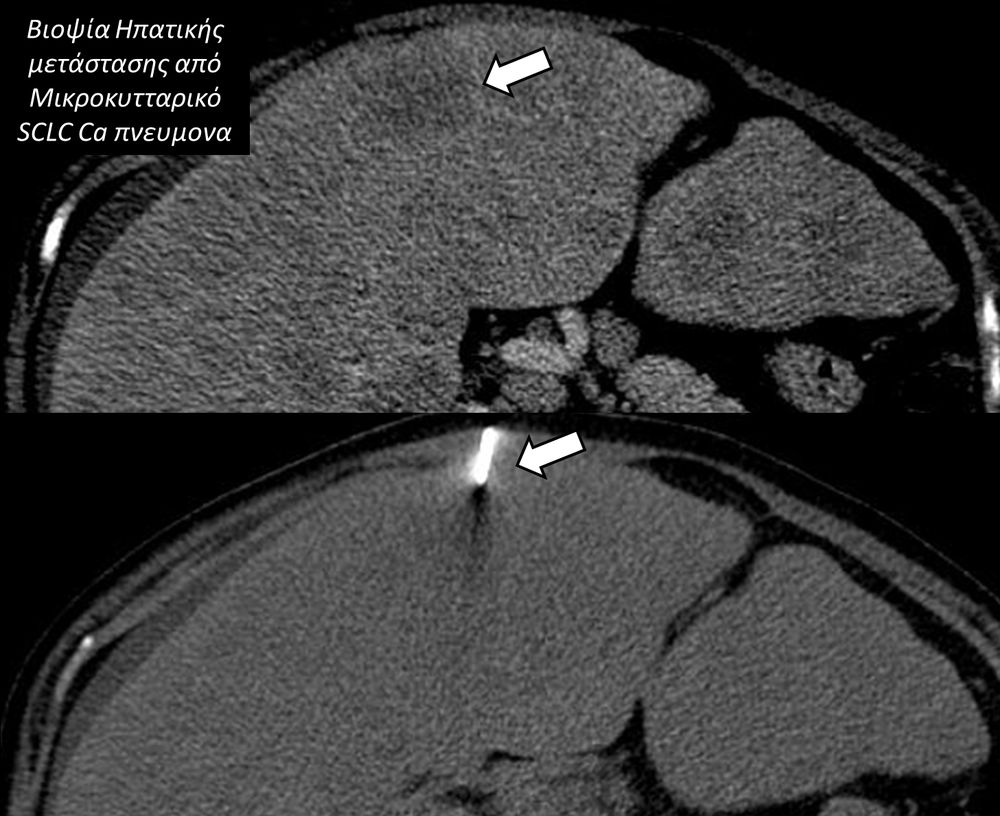

Η διαδερμική βιοψία είναι μία ελάχιστα επεμβατική μέθοδος λήψης υλικού από τον όγκο για κυτταρολογική και ιστολογική εξέταση, από εστιακές αλλοιώσεις του ήπατος, πνεύμονα, νεφρού κλπ. Συστήνεται από τον κλινικό ιατρό ανάλογα με το είδος και το μέγεθος της βλάβης και πραγματοποιείται με ασφάλεια από επεμβατικό ακτινολόγο με την καθοδήγηση αξονικού τομογράφου ή υπερήχων. Στη σύγχρονη ογκολογική θεραπεία όπου γίνεται προσπάθεια καταπολέμησης του καρκίνου σε μοριακό επίπεδο κρίνεται αναγκαία η ακριβής ιστολογική ταυτοποίηση του όγκου ώστε να εφαρμοσθεί εξατομικευμένη θεραπεία για το βέλτιστο αποτέλεσμα. Οι κατευθυνόμενες βιοψίες στοχευουν στο να παρέχουν στον κλινικό ογκολόγο το απαραίτο ιστοπαθολογικό υλικό που θα του επιτρέψει να εφαρμόσει την κατάλληλη θεραπεία για τον ογκολογικό ασθενή.